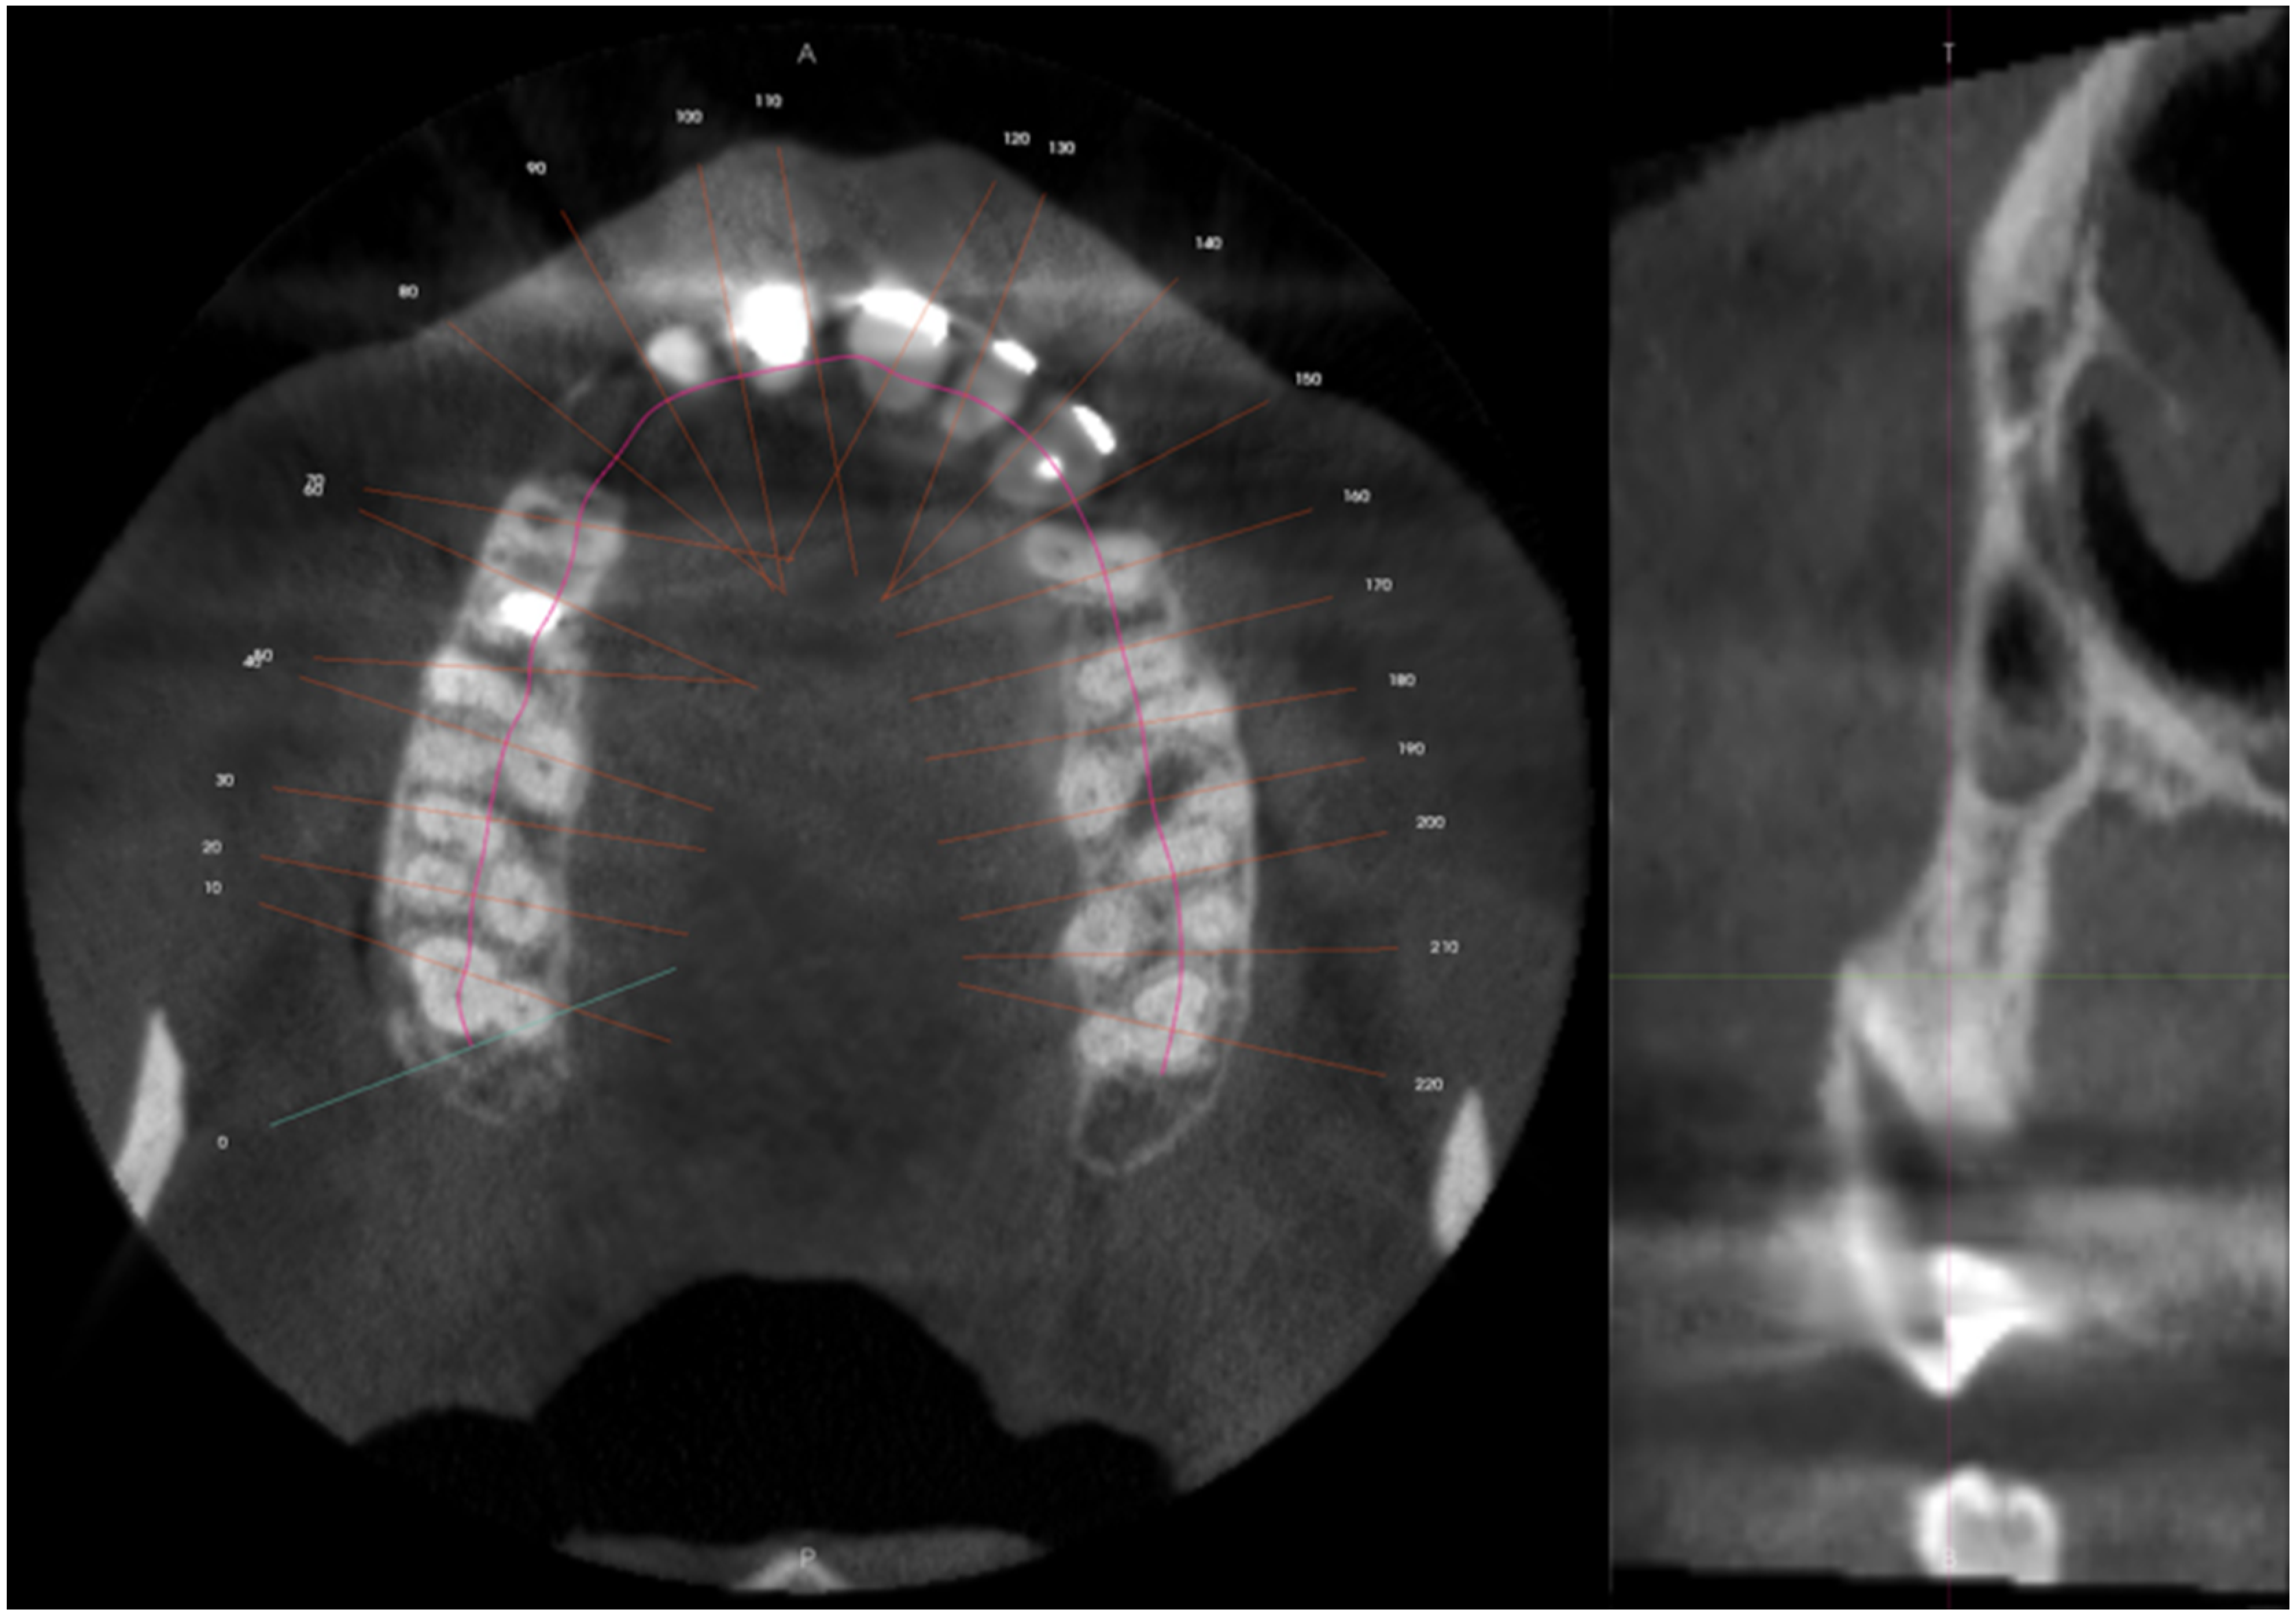

2.1. Report A